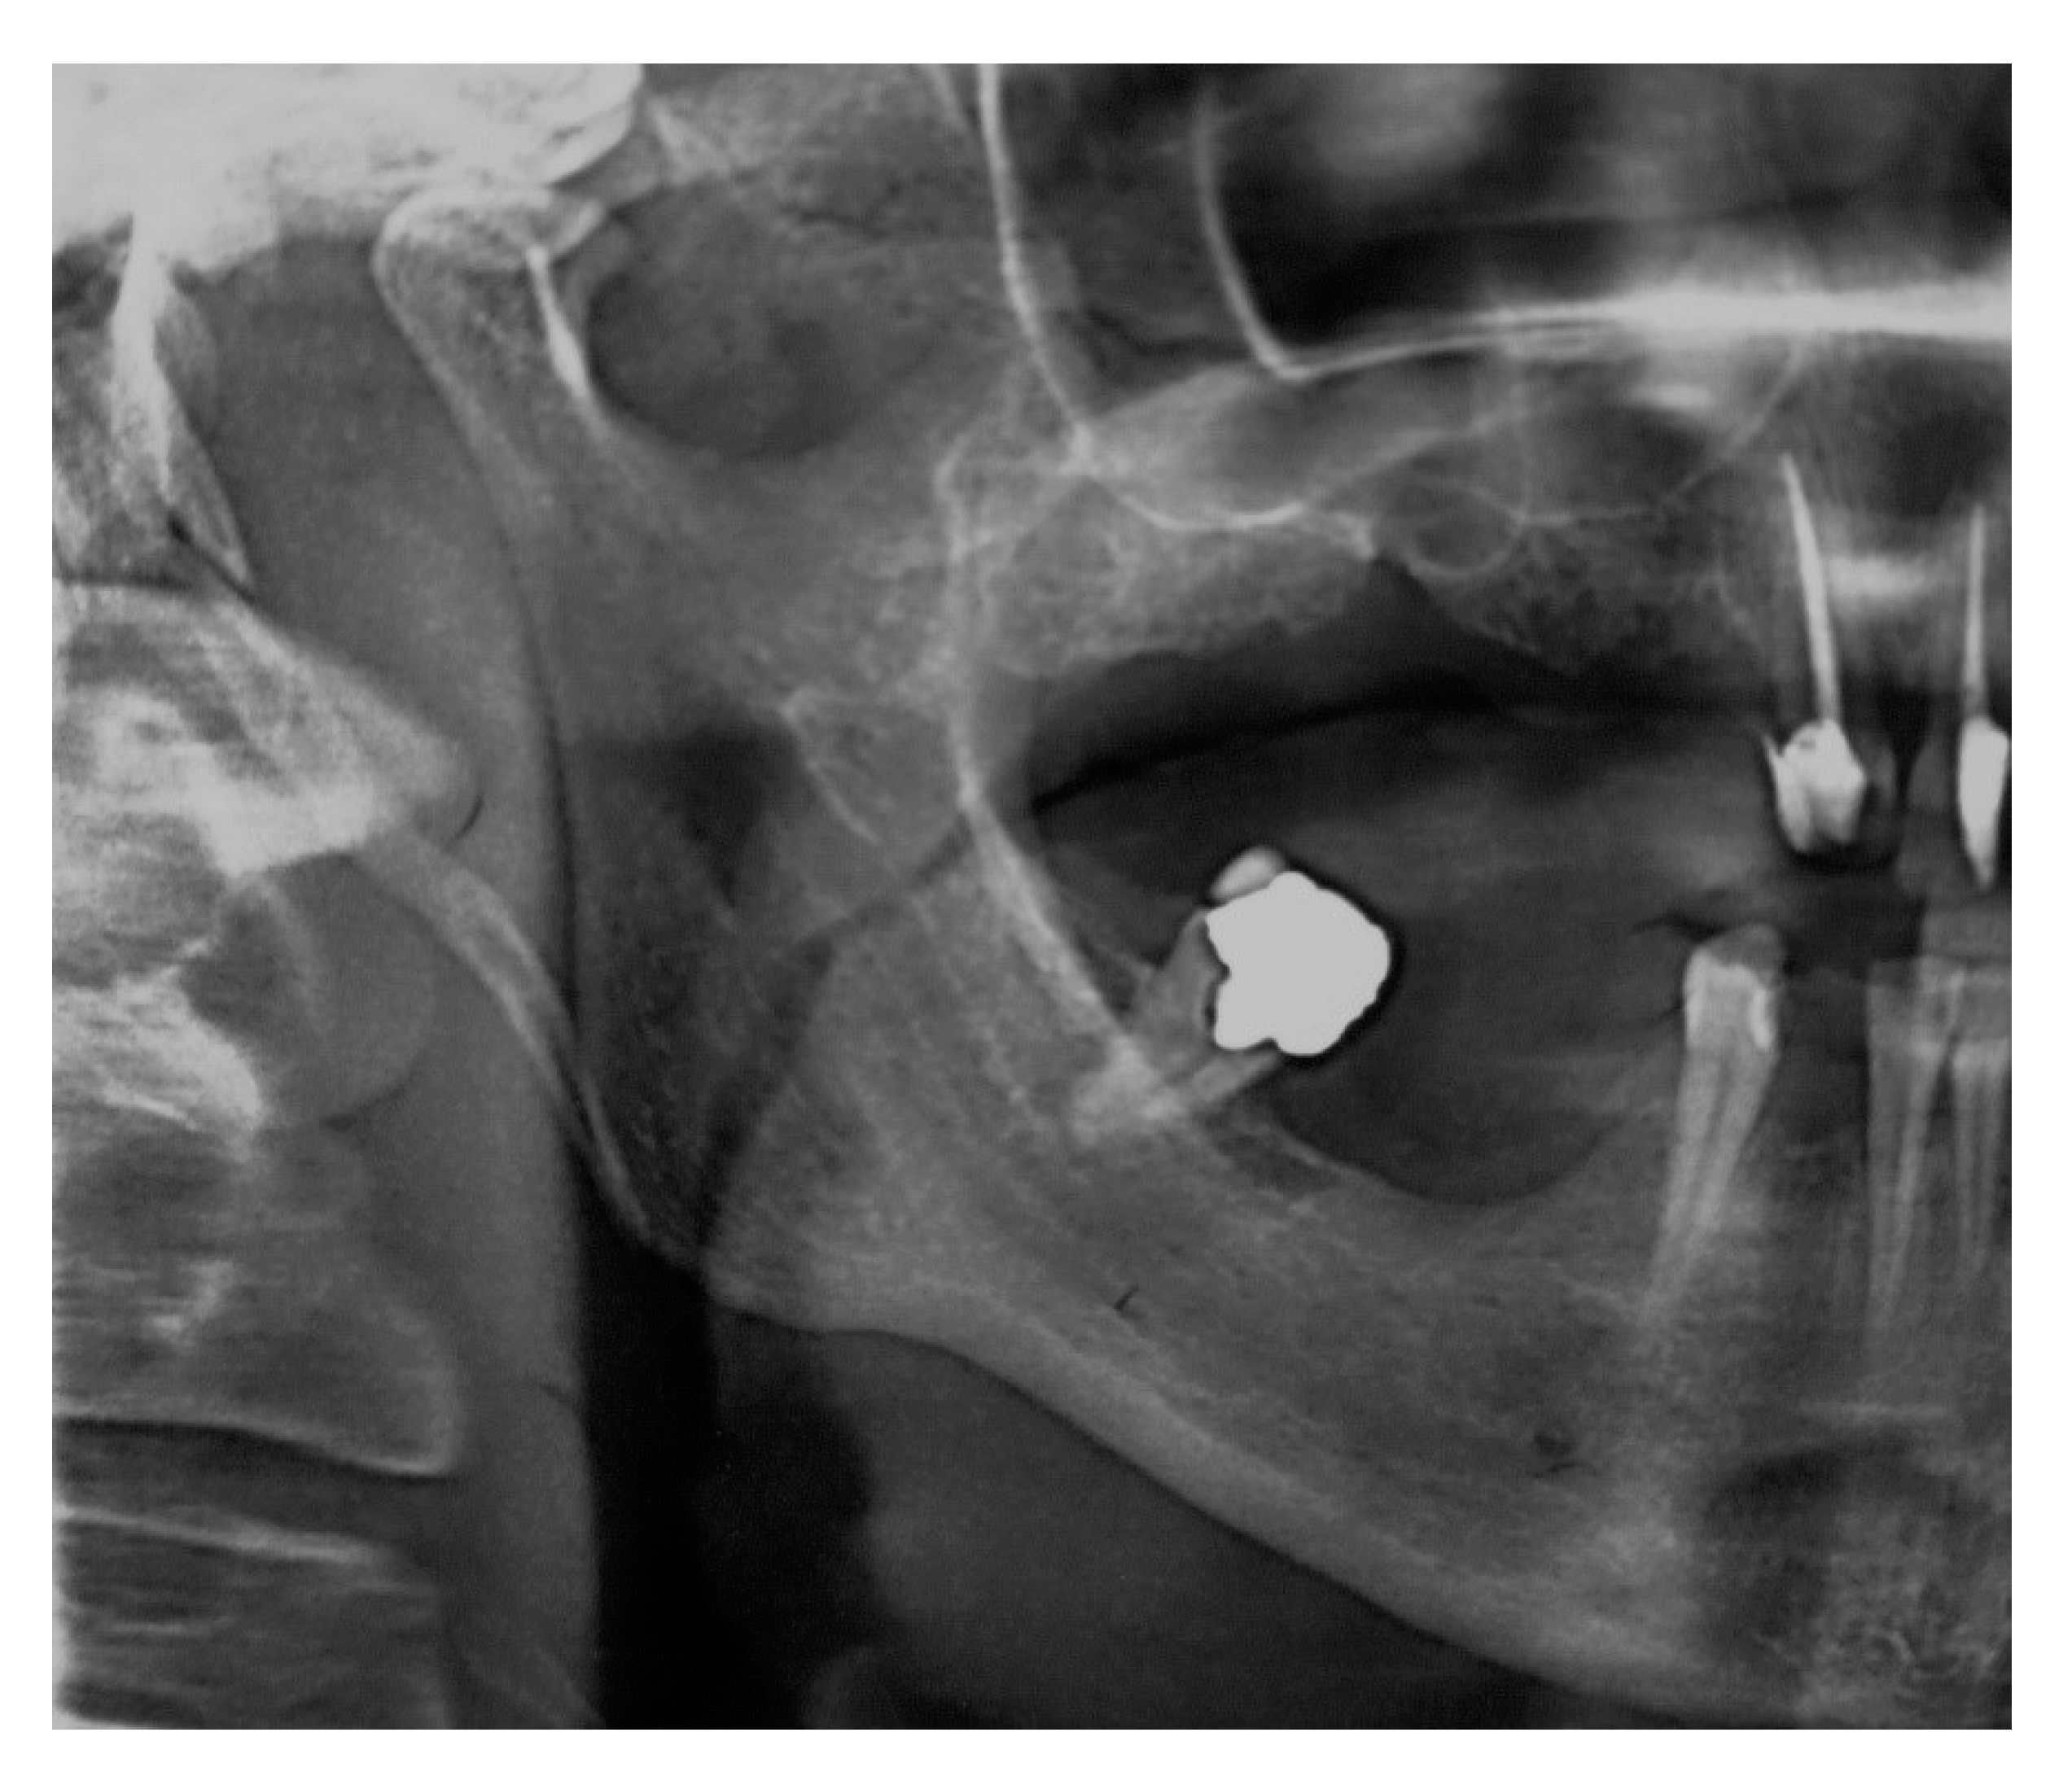

It is a rare condition caused by an elongated or disfigured styloid process which interferes with the functioning of neighboring structures and gives rise to orofacial and cervical pain often triggered by neck movements. I have great insurance so I paid very little of that total although my insurance only paid about half of the total. We report two patients with cerebrovascular symptoms of Eagle syndrome treated in our medical center in the past year.

For language access assistance contact the NCATS Public Information Officer. This procedure called a styloidectomy can be done through the mouth or neck. He first published his data in 1937 with a series of 200 patients presenting with. I think the total for my surgery was 20000-21000. A 47-year-old man present with lump sensation in his left-side throat for few months after UPPP an operation for snoring. The patient became symptom-free at 9 months after the surgery. Surgery to shorten the styloid process is the primary treatment for Eagle syndrome. BACKGROUND Eagle syndrome is an unusual condition in which the styloid process SP becomes elongated and causes different clinical symptoms due to pressure on adjacent anatomical structures. My surgery was billed as a mini-craniectomy.